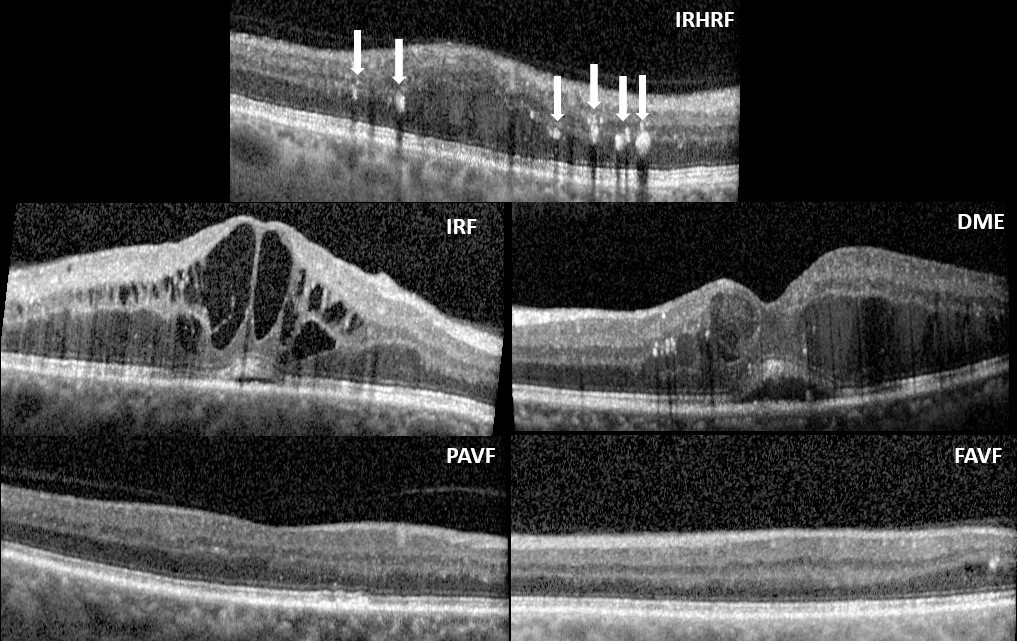

Refer to caption

Figure 7: Cross-sectional images of graded biomarkers. Intra-Retinal Hyper-Reflective Foci (IRHRF), indicated by the six white arrows, are areas of hyperreflectivity in the intraretinal layers with or without shadowing of the more posterior retinal layers. Intra-Retinal Fluid (IRF) encompasses the cystic areas of hyporeflectivity. Diabetic Macular Edema (DME) is the apparent swelling and elevation of the macula due to the presence of fluid. A Partially Attached Vitreous Face (PAVF), with an arrow indicating the point of attachment and a Fully Attached Vitreous Face (FAVF). A discussion of these biomarkers can be found at [58].